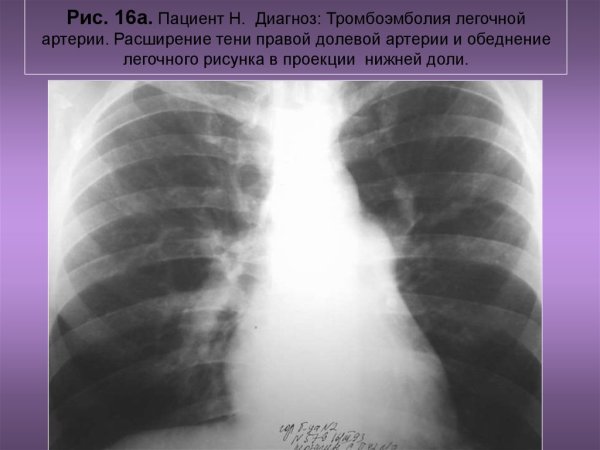

Рентгенография грудной клетки Тэла